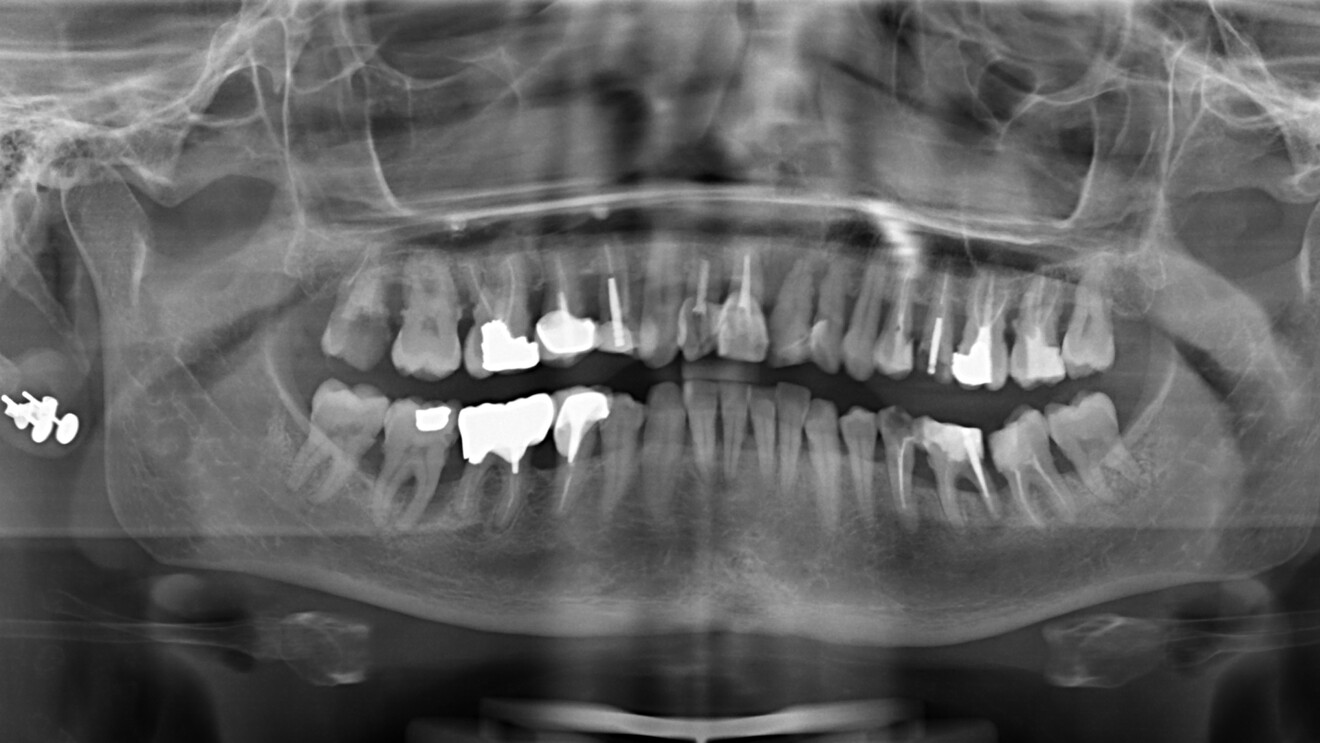

Il s’agit d’une patiente de 48 ans adressée en 2020 par l’un de nos confrères. Ancienne fumeuse, sans problèmes médicaux particuliers, cette patiente présente un long historique parodontal qui, associé à des lésions endodontiques sur 11 et 21, aboutissent à la perte de ses deux incisives centrales (Fig. 7). Cette patiente, active, ne s’est pas fait traiter plus tôt par crainte d’une longue période de temporisation avec une prothèse amovible.

À l’examen la patiente présente en vestibulaire, au niveau de 11 et 21, des pertes de substances importantes (osseuses et gingivales), particulièrement en 21 avec la destruction de l’intégralité de la paroi vestibulaire de la crète, et une perte totale d’ancrage de la racine, ainsi qu’un frein labial inséré haut sur la crête. On conserve néanmoins l’architecture des tissus mous avec la présence de papilles interdentaires et un volume osseux apical suffisant pour permettre l’ancrage des implants (Figs. 8–10). L’enjeux du traitement est de réaliser les extractions, de poser les implants, de reconstruire la crête osseuse, et de mettre en place des provisoires fixes sur les implants, en conservant l’architecture des tissus mous.

Les sutures sont retirées à 15 jours. Un contrôle de la bonne ostéointégration des implants est réalisé à 2 mois postopératoire (Figs. 18 et 19). La prothèse d’usage réalisée par notre correspondant est mise en place à 9 mois postopératoire (Figs. 20 et 21).

La patiente est suivie annuellement (cliniquement et radiologiquement), afin de contrôler l’évolution de l’ankylose des greffons radiculaires, leur résorption ainsi que le bon maintien du volume greffé (recul 48 mois postopératoire [Fig. 22]).